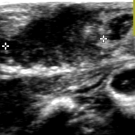

Testicular torsion is a suddenly occurring rotation of a testis about its axis.

04/26/2018